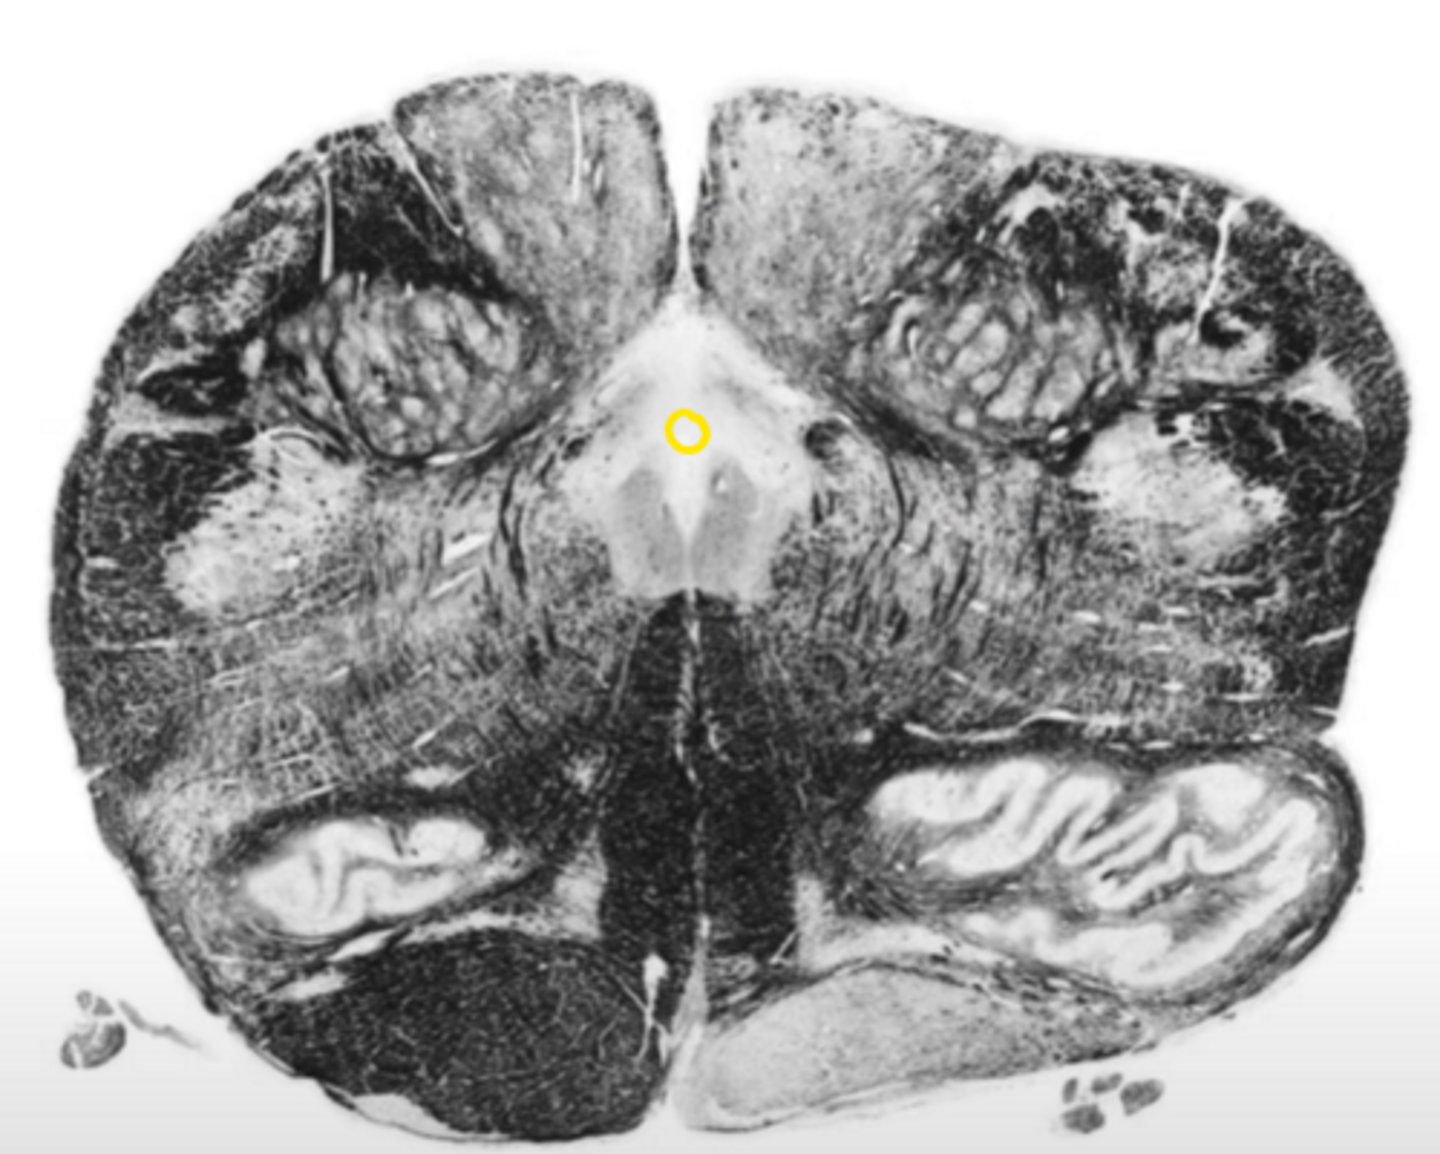

fourth ventricle

ID the space

hypoglossal nucleus

ID the nucleus

vestibular nucleus

inferior cerebellar peduncles

ID the structure

reticular formation

vagus nerve

ID the nerve

principle olivary nucleus

corticospinal fibers

hypoglossal nerve

medial lemniscus

anterior median sulcus